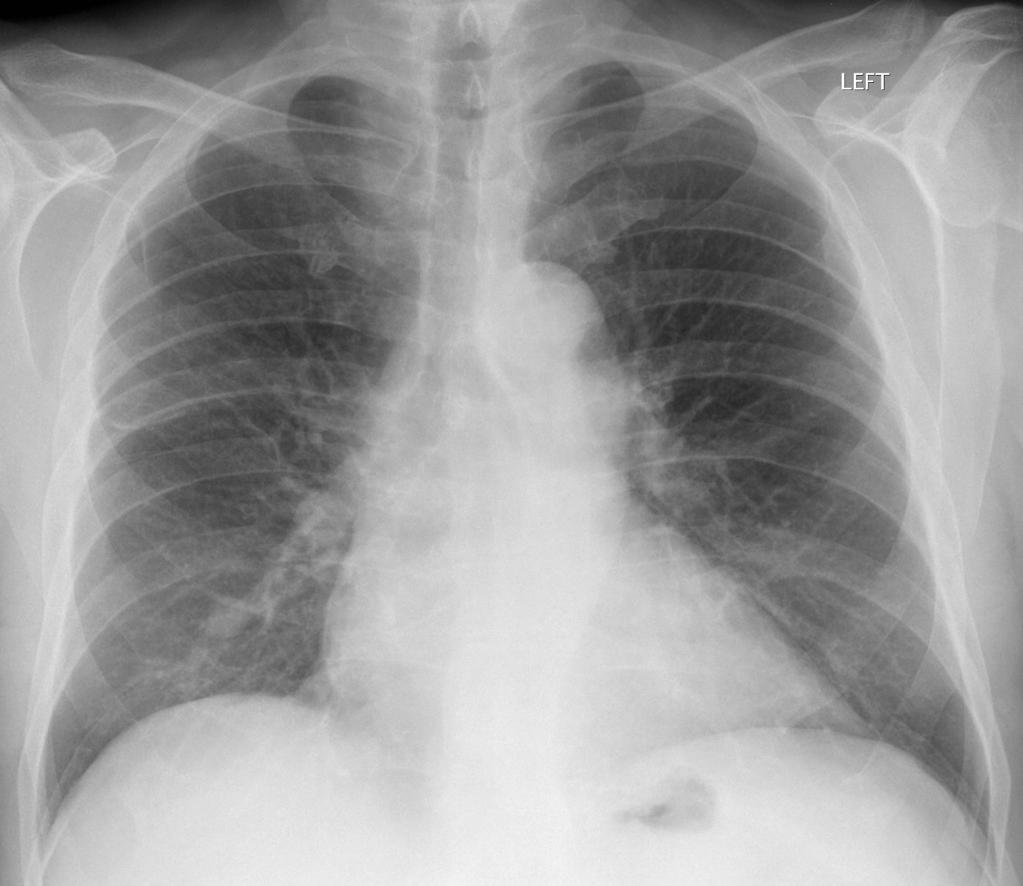

PAINE #PANCE Pearl – Pulmonology Posted by Kristopher Maday PA-C 0 Questions When following low-risk, small single pulmonary nodules, What is the time sequence for the follow-up CT scans? How long do you re-image them for? Radiopaedia Share this: Share on X (Opens in new window) X Share on Facebook (Opens in new window) Facebook Like Loading... Related